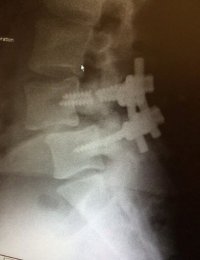

had spinal fusion surgery January 2014, just went back to doc today because I'm now having nerve pain again. two of the four titanium screws broke. bone moved back to hitting my sciatic nerve. he tells me he doesn't want to do another surgery because it's too invasive and he'd have to go through my side instead of the back to get to spine to put in new hardware with a cage and shit. he wanted to refer me to a pain management doc and take pain pills the rest of my life. I said no way. getting a second opinion.

after

ImageUploadedByTapatalk1405657464.944480.jpg

View attachment 54554

Damn bro L4 slid anterior and L5 slid posterior, yeah I know you are having nerve pain for sure my man. Sorry brother